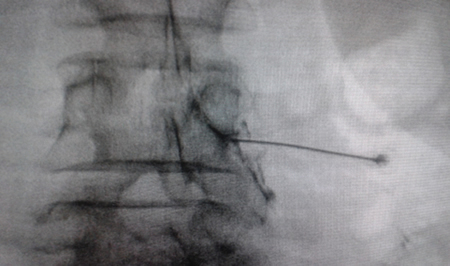

Figure 1